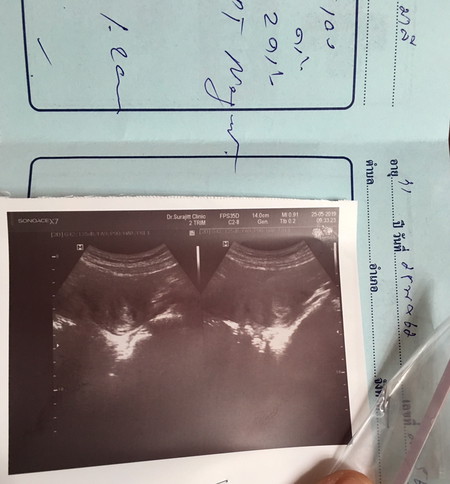

5สัปดาห์

มีใครเคยเป็นแบบนี้บ้างคะ มีเลือดออก สีแดงสด ปวดเหมือนประจำเดือน ตรวจขึ้นจางๆ จะแท้งมั้ยคะ

การตั้งครรภ์ไม่ควรมีเลือดออกนะคะคุณแม่ คุณหมอว่ายังไงบ้างคะ^^